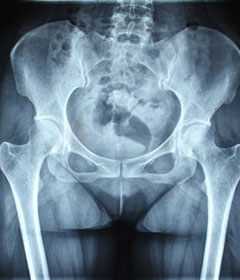

AS ①晚期 ②重度 病史:5年+

- 治疗

治疗后骶髂关节疼痛消失,腰椎前屈、背伸侧弯活动自如,膝关节无压痛感,复查血沉、C反应蛋白、等各项检查均已达到临床康复的标准。